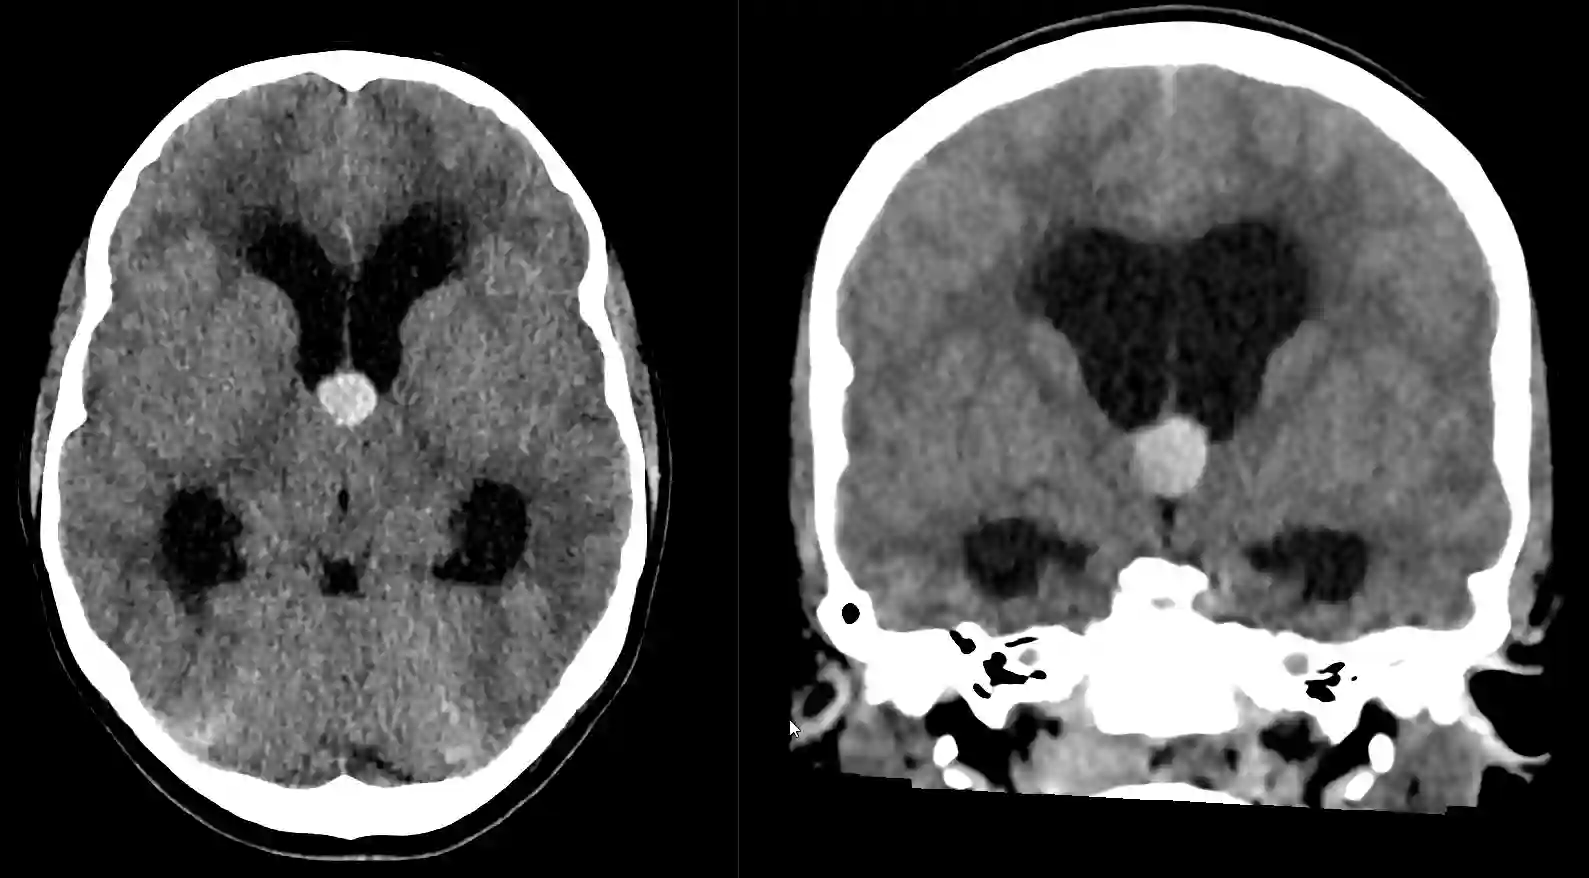

Kolloidzysten können in einer CT oder MRT Bildgebung dargestellt werden, wo sich die Zyste üblicherweise im anterioren Anteil des dritten Ventrikels befindet. In der MRT als auch CT Bildgebung zeigen sich Kolloidzysten variabel jedoch üblicherweise wie folgt[^2]:

CT Bildgebung

Kalzifizierungen werden bei Kolloidzysten nur selten beobachtet[^2].

CT nativ | CT mit Kontrastmittel |

Hyperdens | Ca. 50 % zeigen ein leichtes Enhancement |